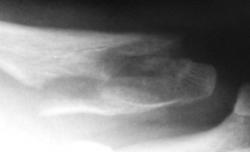

Травма. Перелом ключицы.

Валентин Львович, а какой механизм травмы? смущают контуры отломков - нет ли здесь очагов деструкции с патологическим переломом?

Имхо травматический перелом.

Механизм не скажу, врать не буду. Но этот случай был в моем "запаснике" и еще не выставлялся. Решил выставить, хотя перелом давно весьма успешно консолизировался и даже без деформации ключицы.

значит была неправа - не показалась З-образная линия перелома, хотя теоретически, если была киста, то она при переломе могла самоизлечиться